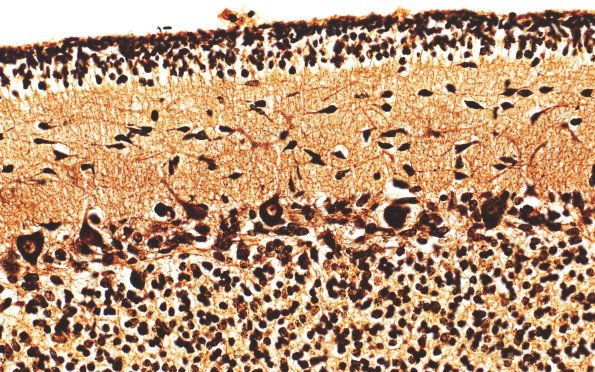

Washington University Experience | METABOLIC | Menkes disease | 4C3 Menkes Dz (Case 4) Biels 40X 1

Bielschowsky silver stained tissue also fails to demonstrate dystrophic Purkinje cell dendrites or axonal “torpedoes” (i.e., axonal spheroids). (Bielschowsky stain)